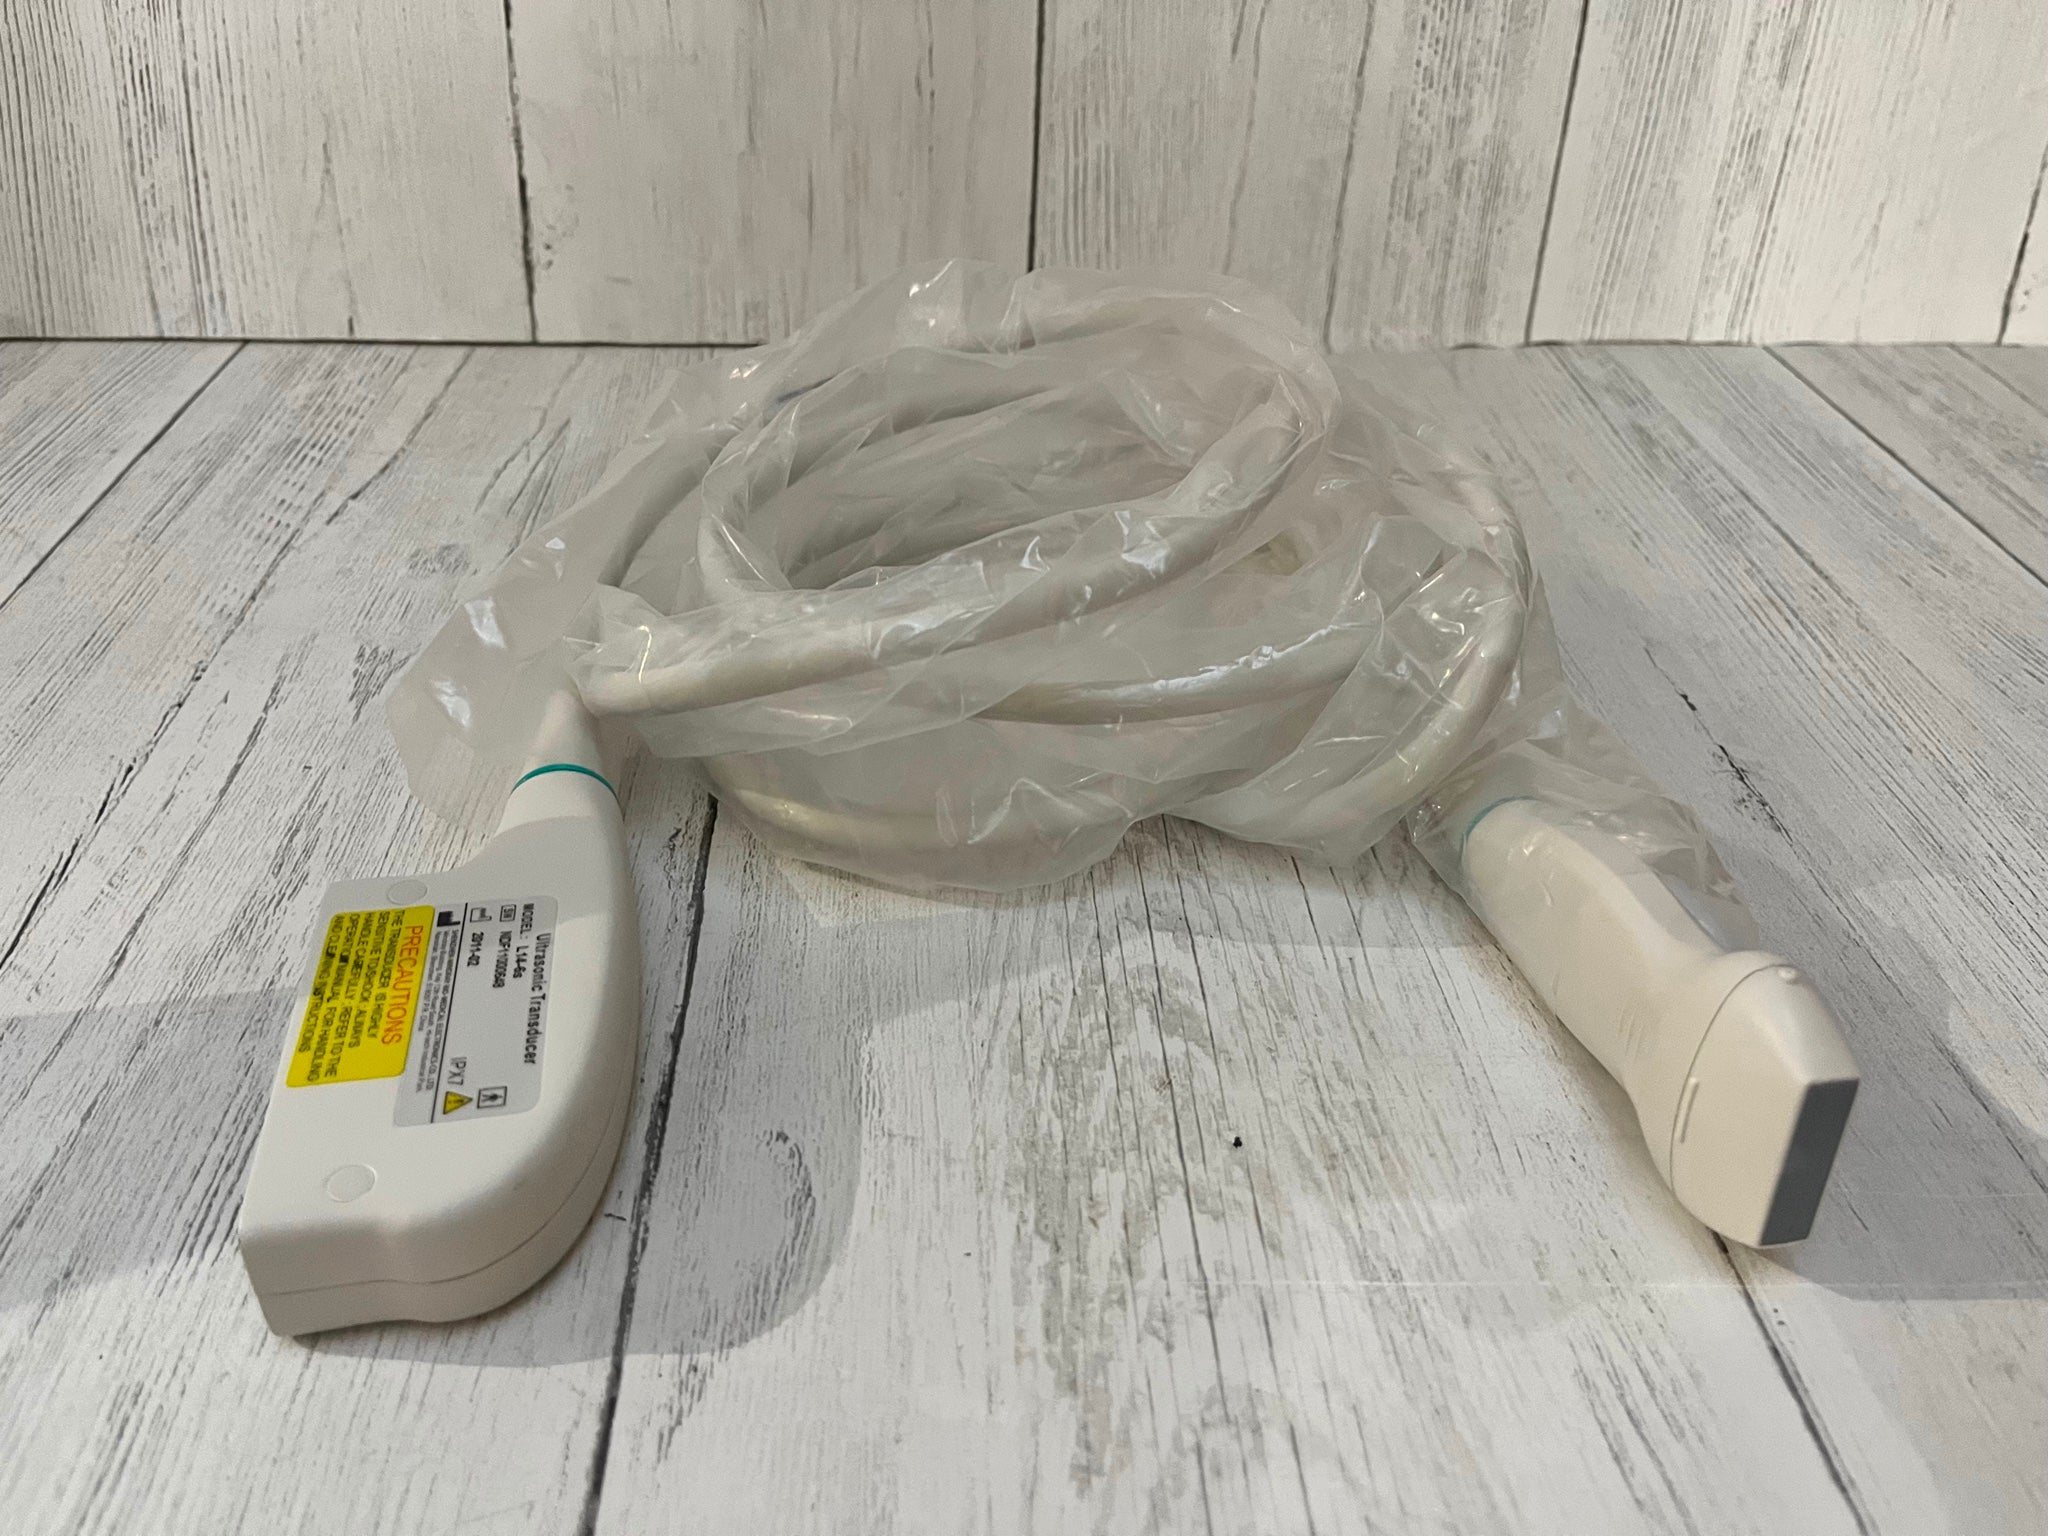

Connectors: 2 probe connectors

Image mode: B, B/B, 4B, B+M, M